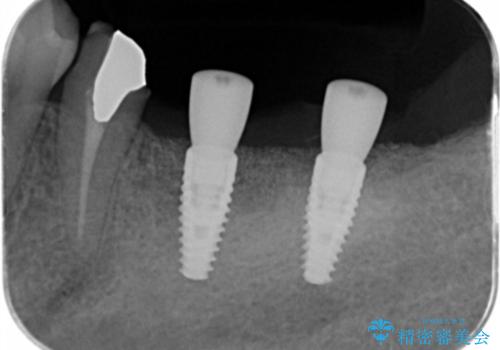

精査をしたところ、歯の破により残すことが難しい状況で、親知らずと共に抜去を行いインプラントによる機能回復を計画します。

- 110万円(インプラント×2・チタンカスタムアバットメント×2・ジルコニアクラウン×3・仮歯×3 ・遊離歯肉移植術)費用は治療当時の料金となります

インプラント周囲のお掃除のしやすさを高め、長期的な予後を見込むために、遊離歯肉移植術を行っています。